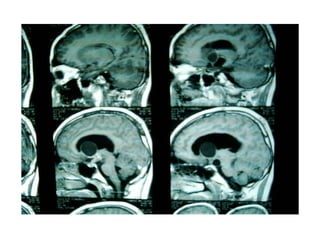

Investigation U ltrasonography to visualize the ventricular system(when the anterior fontanelle is patent). Also for antenatal diagnosis CT and /or MRI of the head; it is important to exclude any abnormal masses and to study the size and the shape of the ventricles, and some time needs contrast study.  LP in cases of communicating hydrocephalus for both diagnostic and therapeutic…..( NPH)

Investigation U ltrasonographyto visualize the ventricular system(when the anterior fontanelle is patent). Also for antenatal diagnosis CT and /or MRI of the head; it is important to exclude any abnormal masses and to study the size and the shape of the ventricles, and some time needs contrast study. LP in cases of communicating hydrocephalus for both diagnostic and therapeutic…..( NPH)